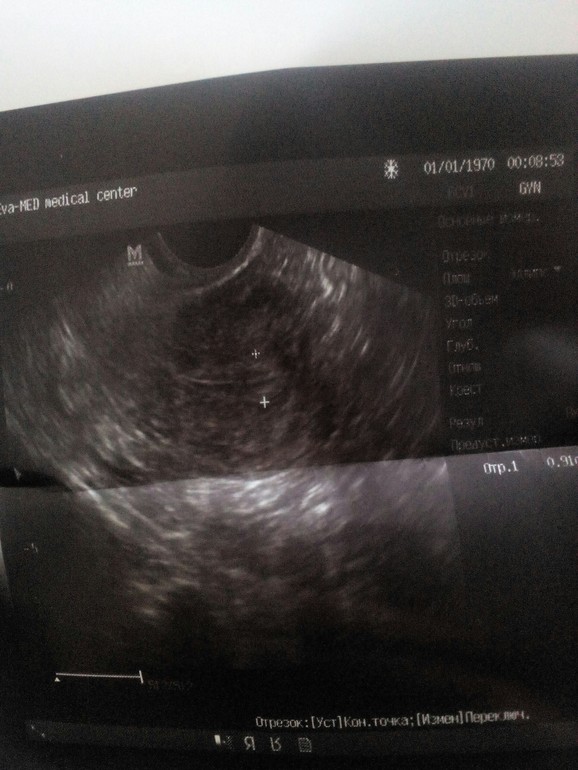

Эндик 0.91см-трёхслойный как положенно в первой фазе,а вот фоллики не поняла все 6-8 до 1,5см??Или их 6-8 и один из низ домминант 1,5?Нужно в таких случаях у них уточнять

Все написано правильно! Антральные фолликулы это не Доминантный, а антральный! Это те которые показывают запас яйцеклеток. Один из этих может начать расти с начала цикла и станет доминантом. Их количество может меняться в каждом цикле. Судя по этому узи запас хороший. Все в норме, эндометрий хороший, а овуляции не было и не будет уже скорей всего, потому что уже 12дц, а в яичниках только антральные фоллики.

Вот спасибо) А овуля будет и скорей всего сегодня- завтра, у меня она ещё ни разу не была на 14 дц чаще на 17 В левом яичнике фолик 1,5 вот на него надежда)

Просто в заключении написано, что они все там до 15мм. Если кто то из них дорастет, то конечно овуля и будет. Чтоб впустую не лелеять надежду, потом можно сходить и глянуть дней через 5, есть ли жт.

Спасибо) Я просто когда делала узистка говорила об одном большом, и сказала что дня 2-3 ему надо ещё что бы подрости

Она просто не написала про дф. Значит все будет! Размер хороший! Должнн вырасти!!! Удачи!!! 🤗

ДФ - 1,5 см, М эхо - это и есть эндометрий, норм для такого размера фолика, все в порядке, О будет через 3-4 дня